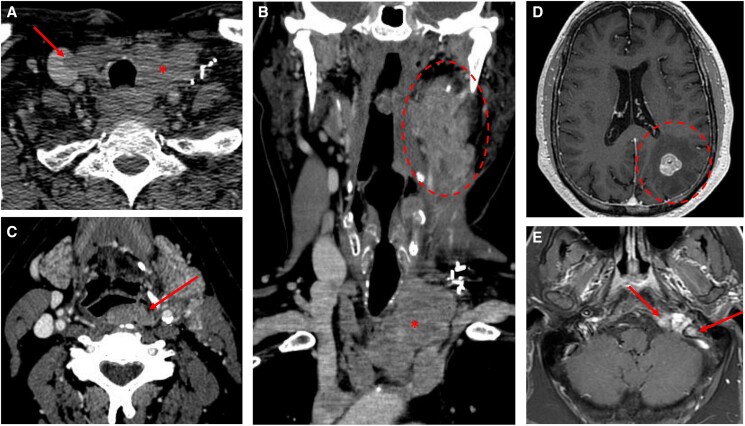

A 65-year-old patient presented with recurrent, locally advanced poorly differentiated thyroid cancer despite 2 neck surgeries, and with newly diagnosed brain and skull base metastases. He was treated with palliative stereotactic radiosurgery to the brain and skull base lesions. Thereafter, as no targetable genetic alteration was identified and antiangiogenic multikinase inhibitors were deemed at high risk of hemorrhagic complications, off-label systemic therapies were considered. The mechanistic target of rapamycin (mTOR) inhibitor everolimus could not be obtained due to lack of insurance coverage, so the patient was treated with single-agent pembrolizumab. He showed an initial remarkable response, but unfortunately had disease progression in the neck and upper mediastinum after 1 year of therapy. At that time, he was treated with external beam radiotherapy, with concomitant pembrolizumab. He was then found to have an CTSB::ALK fusion, which has previously been described in 2 cases of thyroid cancer. However, as he showed a positive response to radiation with pembrolizumab, he continued single-agent immune checkpoint inhibition and had a persistent marked response almost a year after completing radiation. The patient was then followed at an outside institution and was transitioned to hospice at time of progression per his preference. He died 4 years after his initial diagnosis.

Abstract Image